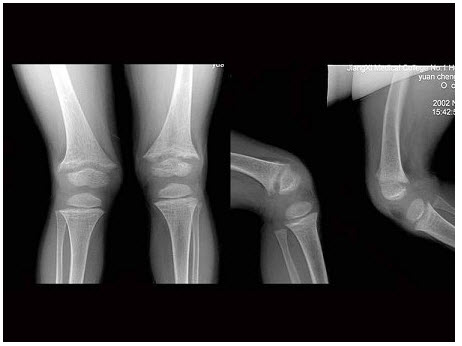

男,37岁,右手腕部外伤1.5小时,右腕部肿痛。根据右腕关节正侧位片,应诊断为()

A.Barton骨折

B.Colles骨折

C.Smith骨折

D.Monteggia骨折

E.Bennett骨折